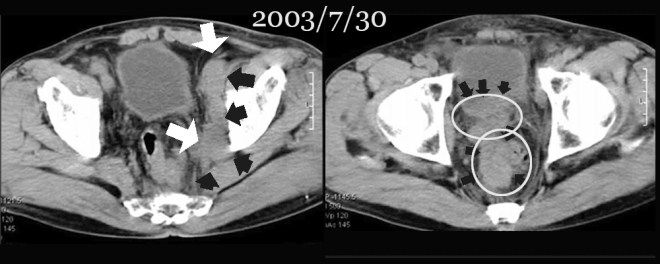

• 2017/4 : 혈뇨 발생하여 방광암 진단

• 2017/4/18 : CT와 조직검사(papillary urothelia carcinoma, high gradeT4)

• 2017/4/26 한의원 내원 – 한방약물 G0054 시작

• 2017/4/26 영상의학과 초음파 검사 62.9 ml 체적

• 2017/5/12 영상의학과 초음파 검사 56.6ml 체적- 종양 10% 감소

• 2017 /5/2+  방사선 치료 시작

• 2017/5/26 영상의학과 초음파 검사 41.6ml 체적 – 종양 33% 감소(방사선 치료 4일. 한약치료 30일결과)

이  환자의  초기 병원 검진 상태는 다음과  같다.

이의 CT 자료는 다음과 같다.

이장호 1-8.JPG

unresectable  bladder  tumor

수술이 불가하며 방광의 좌측 윗벽 후벽 아래벽을 모두 침범한 방광암으로 요관과 방광의 이음부까지 침범하여서 수신증이 심하였다. 조직검사는 papillary urothelial carcinoma로 high grade의 종양으로 판명되었다.

2017년 4월 26일 반룡인수한의원에서 초기 진료를 하였다. 그리고 한달 동안 한약을 복용하였다. 나는 방사선종양학과에 의뢰하여서, 이 환자는 방사선 치료를 4일 정도 받았다. 그리고 한달 만에다시금 체크를 하였다. 초기에 혈뇨로 인하여서 방광암을 발견하였다. 그리고 초기에 조직검사시에 피가 나왔다. 이 피는 일주일 만에 그쳤다. 그리고 한약 G0054(herbal medication)을 복용한 후에 소변이 차차 깨끗해지고 맑아졌다. 이후 한 차례 정도 피가 나오고 그쳤다.

초기의 한의원 방문 시에 검사한 방사선 자료와 한달 뒤의 자료를 비교해 보겠다.

이장호 1-3.JPG

초기에 한의원을 방문할 당시의 전문영상의학과 초음파 검사 자료에 의하면 요관은 수신증 때문에 12mm 정도 확장이 되어 있다. 그리고 종양의 전체 면적은 62.9cc로 측정되었다.

이장호 1-4.JPG

이 환자는  2주간 한약치료(herbal medicatio G0054)를 받았다. 다른 양약의 조치는 없었다. 그리고 서울대에서 조직검사 결과를 기다리는 중이었다.

2주 뒤에 초음파 검사의 결과는 다음과 같다. 약 4mm 정도의 종양이 감소를 보였다. 그래서 전체 volume의 10% 정도가 감소되었다. 2017/4/26일에 62.9ml의 체적이 2017/5/12일에는 56.6 ml 로 감소되었다. 이렇게 빠르게 검사하는 데는 특별한 이유가 있다. 나의 개인적인 견해로는 방사선 치료는 태음인(太陰人 autumn type)에게는 적합하지만, 소음인(少陰人winter type)에게는 오히려 해로울 수도 있다고 생각한다. 많은 경우에 소음인 암환자들이 방사선을 치료 받은 후에 일시적으로 종양의 괴사를 가져온다. 하지만 한 두달이 지나면 오히려 암세포를 자극하여서 종양이 다시 재발하거나 무섭게 다른 곳으로 퍼지는 경우를 나는 많이 겪어 보았다. 그래서 꼭 필요한 경우, 방사선 조치로 암을 물리적인 억제를 해야 하는 경우가 아니라면, 소음인에게는 방사선 치료를 권유하지 않는다. 또한 소음인은 방사선 치료에 대해서 잘 견디지 못한다. 매우 힘들어하고 체력이 떨어지고 한다. 항암에서 부작용이 적게 나던 소음인들조차도, 방사선 치료가 훨씬 어렵다는 이야기들을 자주 한다. 반면에 태음인들은 거의 부작용이 나타나지 않는다. 일상생활을  다 하면서도 태음인(太陰人 autumn type)들은 방사선 치료를 받으러 다닌다. 그래서 약 2주간의 한방약물 G0054의 치료 후에 결과를 살펴 보았다. 이는 체질에 대한 분류에 오류를 좁히는 방법도 된다. 나의 분류가 맞았고, 약물이 정확하게 반응했다면 종양은 조금이라도 감소를 보일 것이다.  그러나 나의 체질 분류가 틀렸다면 종양은 오히려 더 커지거나 나쁜 영향을 줄 것이다. 이러한 연유로 인하여서 나는 빠른 추적검사를 하였다. 또한 이러한 결과를 통해서  앞으로 어떻게 치료를 할 것인지에 대한 생각을 정리할 수 가 있다. 이 환자는 한방 단독요법만 할 것인가? 아니면 항암치료도 병행할 것인가? 다행히도 이 환자는 종양의 체적이 10% 가량 줄어들었다. 이로써 나는 더욱 체질분류에대한 확신을 할 수 있었다. 그래서 환자에게 자신있게 방사선 치료를 병행할 것을 권유하였다.

이장호 1-5

그리고 환자는 아직 방사선 치료는 4일밖에 받지 못 하였고, 한약(herbal medication G0054)은한달간 복용하였다. 그리고  2017년 5월 26일 나의 clinic에서 한달간 치료 후의 결과를 다시 추적검사를 하였다. 종양은  41.6ml로 감소되었다. 초기의 종양 크기인 62.9ml에서부터 약 33 %의 체적의 감소를 보였다.  또한 환자는 방사선치료를 하는 동안 아무런 부작용도 느끼지 못하였다.  그래서 말하길 “이렇게 아무렇지도 않으면 과연 치료효과가 있을까”라는 의심을 하였다고 한다.

이 환자는 2017년 5월 31일 방사선 치료 전에 찍은 CT 사진을 가지고 왔다. 그래서  오늘 상담을 하고 이전 최초 발견한 2017년 4월 13일과 한방치료를 한달 가량 받고 아직 방사선 치료를 시작하기 전인  2017년 5월 22일 사진을 비교하였다. 내가 방사선 전문가가 아니기 때문에 전체 체적을 볼 수는 없고, 단지 CT 상 같은 부위를 불규칙한 방광을 침범한 종양의 두께를 재어서 비교를 하였다. 그리고 이는 나의 clinic에서 사용한 한약이 방광에 어떠한 영향을 주었는가를 알 수 있는 자료이다. 독자들은 참고 하시기 바란다.

이장호비교.jpg